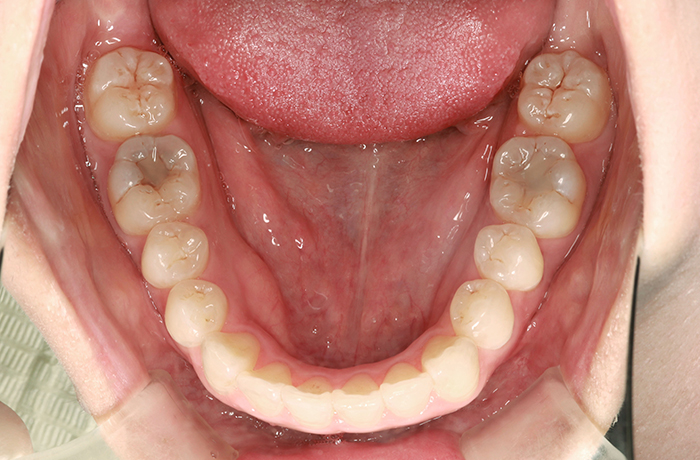

M様

治療前

before

年齢 21歳

性別 男性

治療名称 マウスピース型カスタムメイド矯正歯科装置(インビザライン)・コンプリヘンシブパッケージ(フルパッケージ)

総額治療費用 770,000円(税込10%) 金額備考 精密検査料・診断料 33,000円(税込10%)

治療期間 1年 通院頻度など 1か月ごと

患者の症状 上顎前突、前歯離開

治療方法 マウスピース型カスタムメイド矯正歯科装置(インビザライン)による矯正

治療結果 歯列改善、咬合状態が良くなりました。

リスク/副作用 20時間以上、装置の装着時間が必要です。